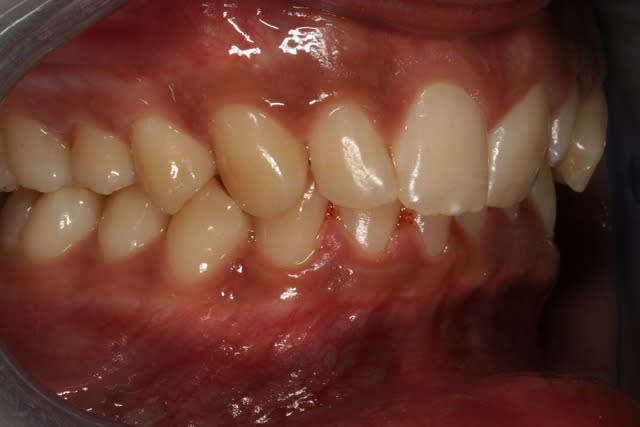

ce jeune (20 ans) patient que je vois pour la première fois me dis que ces gencives, depuis 3-4 mois prennent cette couleur plus marron en antérieur, et que ça a progressé petit à petit du centre vers les cotés

mélanose tabagique? Il est sûrement fumeur, arrêt de fumer et couleur normal revient au bout de 6 à 9 mois

il est fumeur? combien de cigarettes par jour?